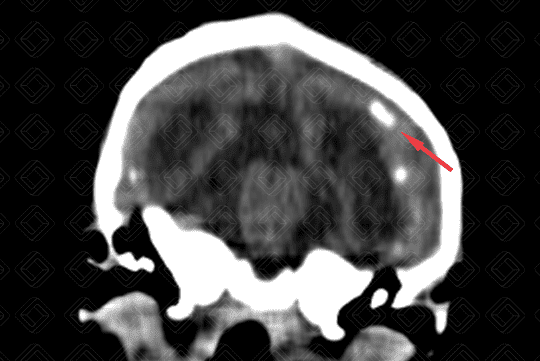

• Observa-se a presença de calcificações de distribuição corticossubcortical (setas vermelhas) no parênquima encefálico e algumas menos evidentes, nos núcleos da base;

• Na última imagem, reconstrução tridimensional (3D) do mesmo paciente confirma a microcefalia e evidencia o cavalgamento das suturas coronais e a perda do ângulo frontonasal.

• Tomografia computadoriza do crânio : No zika vírus, alguns achados tomográficos podem auxiliar a confirmar a suspeição clínica, como: microcefalia; protuberância de pele na região occipital externa; redução do ângulo frontonasal; excesso de pele na região occipital; cavalgamento de suturas; fechamento precoce da fontanela anterior; distúrbio de migração neuronal; atrofia cerebral difusa; calcificações. Padrão das calcificações: costumam distribuir-se na transição do córtex com a substância branca (região corticossubcortical) e, menos comumente, nos núcleos da base e tálamos;